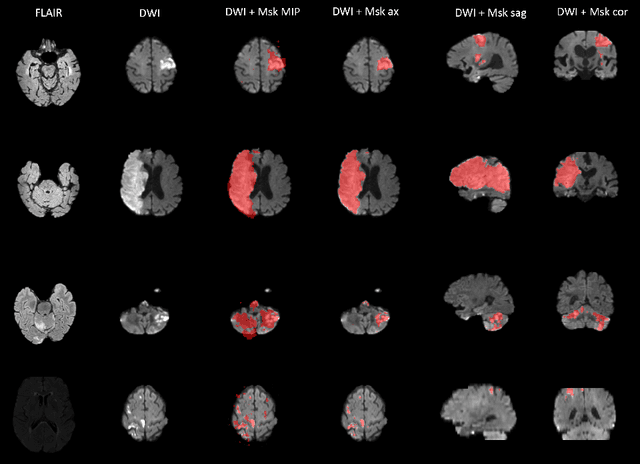

Abstract:Diffusion-weighted MRI (DWI) is essential for stroke diagnosis, treatment decisions, and prognosis. However, image and disease variability hinder the development of generalizable AI algorithms with clinical value. We address this gap by presenting a novel ensemble algorithm derived from the 2022 Ischemic Stroke Lesion Segmentation (ISLES) challenge. ISLES'22 provided 400 patient scans with ischemic stroke from various medical centers, facilitating the development of a wide range of cutting-edge segmentation algorithms by the research community. Through collaboration with leading teams, we combined top-performing algorithms into an ensemble model that overcomes the limitations of individual solutions. Our ensemble model achieved superior ischemic lesion detection and segmentation accuracy on our internal test set compared to individual algorithms. This accuracy generalized well across diverse image and disease variables. Furthermore, the model excelled in extracting clinical biomarkers. Notably, in a Turing-like test, neuroradiologists consistently preferred the algorithm's segmentations over manual expert efforts, highlighting increased comprehensiveness and precision. Validation using a real-world external dataset (N=1686) confirmed the model's generalizability. The algorithm's outputs also demonstrated strong correlations with clinical scores (admission NIHSS and 90-day mRS) on par with or exceeding expert-derived results, underlining its clinical relevance. This study offers two key findings. First, we present an ensemble algorithm (https://github.com/Tabrisrei/ISLES22_Ensemble) that detects and segments ischemic stroke lesions on DWI across diverse scenarios on par with expert (neuro)radiologists. Second, we show the potential for biomedical challenge outputs to extend beyond the challenge's initial objectives, demonstrating their real-world clinical applicability.

Abstract:Magnetic resonance imaging (MRI) is a central modality for stroke imaging. It is used upon patient admission to make treatment decisions such as selecting patients for intravenous thrombolysis or endovascular therapy. MRI is later used in the duration of hospital stay to predict outcome by visualizing infarct core size and location. Furthermore, it may be used to characterize stroke etiology, e.g. differentiation between (cardio)-embolic and non-embolic stroke. Computer based automated medical image processing is increasingly finding its way into clinical routine. Previous iterations of the Ischemic Stroke Lesion Segmentation (ISLES) challenge have aided in the generation of identifying benchmark methods for acute and sub-acute ischemic stroke lesion segmentation. Here we introduce an expert-annotated, multicenter MRI dataset for segmentation of acute to subacute stroke lesions. This dataset comprises 400 multi-vendor MRI cases with high variability in stroke lesion size, quantity and location. It is split into a training dataset of n=250 and a test dataset of n=150. All training data will be made publicly available. The test dataset will be used for model validation only and will not be released to the public. This dataset serves as the foundation of the ISLES 2022 challenge with the goal of finding algorithmic methods to enable the development and benchmarking of robust and accurate segmentation algorithms for ischemic stroke.